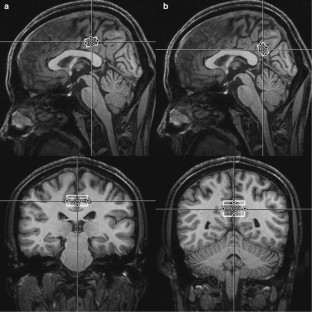

Fig. 2